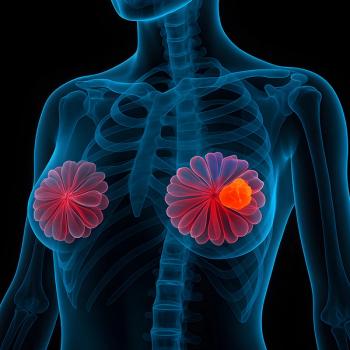

Adding aprepitant to chemotherapy was linked to longer survival in patients with non-luminal breast cancers, especially triple-negative breast cancer.

Understanding actionable mutations and educating patients on the safety profiles of targeted therapies are essential for the care of HR+, HER2- mBC.

If patients with breast cancer have hyperglycemia or symptoms of it at home, a short break from capivasertib may be required, according to Hope Rugo, MD.

New therapies in breast cancer, particularly ADCs, present unique safety profiles for nurses to be aware of, according to Erika Hamilton, MD.

Data from a research database link ctDNA positivity in early breast cancer with poorer survival and higher recurrence risk.